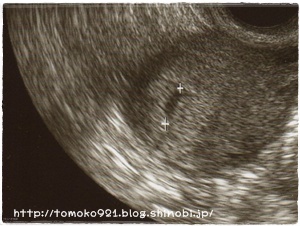

8月18日に、病院に行ってみると・・・胎嚢を確認!

090818.jpg

しかし、この時点では赤ちゃんは見えず。

このエコー写真を撮った丸2週間後の9月1日にもう一度病院へ行きました。